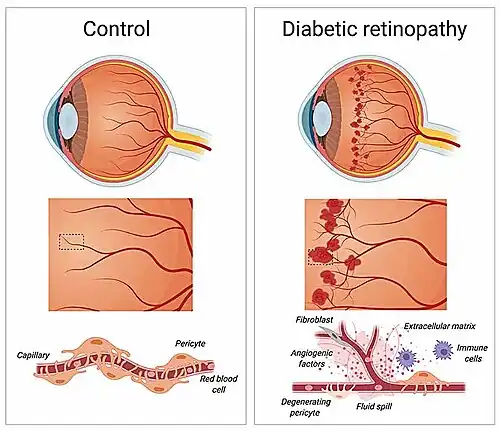

Diabetische retinopathie

Het netvlies van diabetische personen vertoont vaak verlies van pericyten, en dit verlies is een kenmerkende factor van de vroege stadia van diabetische retinopathie. Studies hebben aangetoond dat pericyten essentieel zijn bij diabetische personen om de endotheelcellen van netvlies haarvaten te beschermen. Bij het verlies van pericyten vormen zich microaneurysma's in de haarvaten. Als reactie hierop verhoogt het netvlies ofwel zijn vasculaire doorlaatbaarheid, wat leidt tot zwelling van het oog door een macula-oedeem, of vormt het nieuwe vaten die doordringen in het glasvocht van het oog. Het eindresultaat is vermindering of verlies van het gezichtsvermogen.[41] Hoewel het onduidelijk is waarom pericyten verloren gaan bij diabetische patiënten, is een hypothese dat toxische sorbitol en glycosyleringseindproducten (AGE) zich ophopen in de pericyten. Vanwege de opbouw van glucose verhoogt het polyolpad zijn doorstroom, en hopen intracellulaire sorbitol en fructose zich op. Dit leidt tot osmotische onbalans, wat resulteert in celschade. De aanwezigheid van hoge glucosespiegels leidt ook tot de opbouw van AGE's, die ook cellen beschadigen.[42]

Communicatie tussen endotheelcellen en pericyten is van vitaal belang. Het remmen van het PDGF-pad leidt tot pericytdeficiëntie. Dit veroorzaakt endotheelhyperplasie, abnormale verbindingen en diabetische retinopathie.[41] Een gebrek aan pericyten veroorzaakt ook een upregulatie van vasculair endotheliale groeifactor (VEGF), wat leidt tot vaatlekkage en bloeding.[49] Angiopoietine 2 kan fungeren als een antagonist voor Tie-2,[50] waardoor de endotheelcellen worden gedestabiliseerd, wat resulteert in minder interactie tussen endotheelcellen en pericyten. Dit leidt af en toe tot de vorming van tumoren.[51] Net als de remming van het PDGF-pad verlaagt angiopoietine 2 de niveaus van pericyten, wat leidt tot diabetische retinopathie.[52]